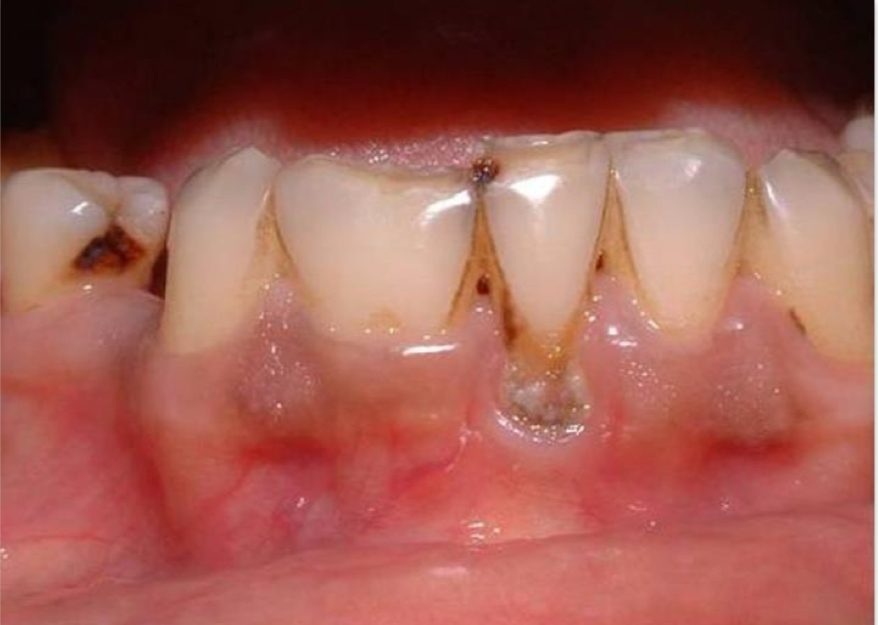

Dens in dente/invaginatus- invagination of enamel

Palatal groove on lingual surface

What are the 3 types of dens invaginatus that are part of Oehlers classification?

1- invagination limited to crown- not beyond CEJ

2- extends beyond CEJ, may/not communicate with pulp

3- extends through root- no communication with pulp